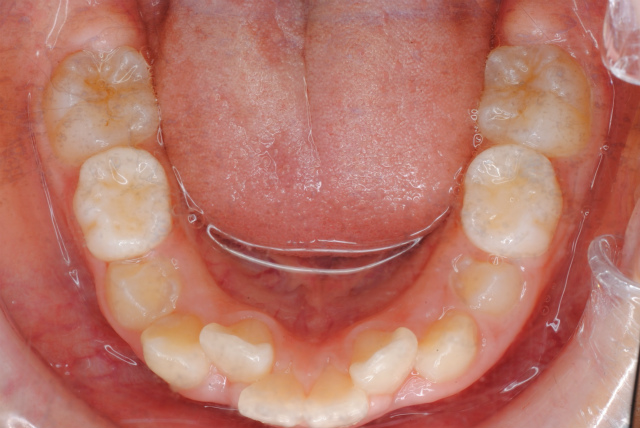

舌がきちんと機能するようになれば、舌側(内側)に倒れていた奥歯がちゃんと頬側に直立して、舌の収まる空間が拡大する、嚥下機能が回復する、発音がしやすくなる、咀嚼効率が上がる、気道が広がる、呼吸が楽になる、歯並びだけでなく上下顎の不調和の改善に多くの成果や効果が見込まれます。

現在 舌挙上のトレーニング中